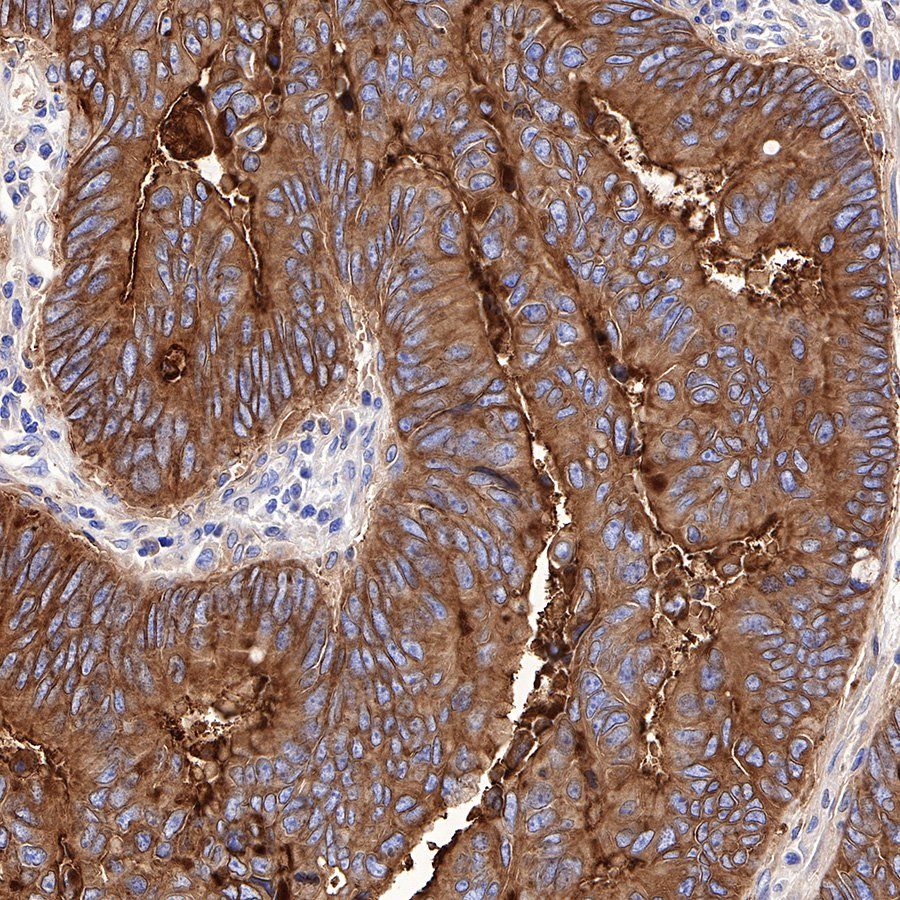

IHC shows positive staining in paraffin-embedded human colon cancer. Anti-CEA(CD66e) antibody was used at 1/1000 dilution, followed by a Goat Anti-Rabbit IgG H&L (HRP) ready to use. Counterstained with hematoxylin. Heat mediated antigen retrieval with Tris/EDTA buffer pH9.0 was performed before commencing with IHC staining protocol.